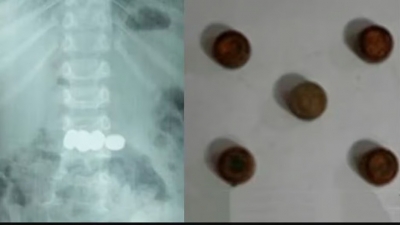

മേപ്പാടിയില്‍ രണ്ട് വയസ്സുകാരന്‍ വിഴുങ്ങിയ അഞ്ച് ബാറ്ററികള്‍ എന്‍ഡോസ്‌കോപ്പിയിലൂടെ പുറത്തെടുത്തു

മേപ്പാടി: കളിപ്പാട്ടത്തിലുണ്ടായിരുന്ന അഞ്ച് കോയിന്‍ ടൈപ്പ് ബാറ്ററികള്‍ വിഴുങ്ങിയ രണ്ട് വയസ്സുകാരനെ എന്‍ഡോസ്‌കോപ്പിയിലൂടെ വിജയകരമായി രക്ഷപ്പെടുത്തി. ബത്തേരി മൂലങ്കാവ് സ്വദേശികളുടെ മകനാണ് അപകടത്തില്‍പ്പെട്ടത്.

- ഡോ. മൂപ്പന്‍സ് മെഡിക്കല്‍ കോളജിലെ ഗാസ്‌ട്രോ എന്ററോളജി വിഭാഗം സ്‌പെഷലിസ്റ്റ് ഡോ. സൂര്യനാരായണയുടെ നേതൃത്വത്തിലായിരുന്നു എന്‍ഡോസ്‌കോപ്പി വഴി ബാറ്ററികള്‍ പുറത്തെടുത്തത്.